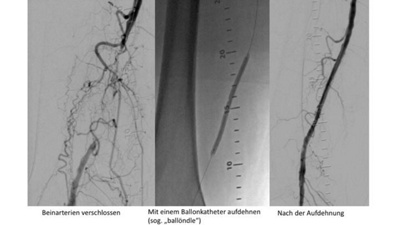

Bei wenig fortgeschrittener Schaufensterkrankheit ist ein überwachtes Gehtraining nebst medikamentöser Behandlung empfehlenswert. Bei schlechtem Ansprechen des Gehtrainings oder Zunahme des Krankheitsbildes kann eine Ballondilatation („ballöndle“) eine Verbesserung herbeiführen. Hierbei wird eine Gefässengstelle oder ein Gefässverschluss in den meisten Fällen minimal-invasiv mit einem Ballonkatheter (Bild 1), Absaugkatheter oder, falls nötig, durch ein kleines Drahtgitternetz, eine sogenannte Stenteinlage (Bild 2), erfolgreich und mit geringem Risiko behandelt. Der Eingriff findet in örtlicher Betäubung statt und die meisten Patienten verspüren während des Eingriffes keine Schmerzen.

Die moderne Ballonkatheter- oder Stenttechnik (Bild 2) hat sich in den letzten Jahren so verfeinert, dass sie mit einem Medikament beschichtet sind, die das Risiko einer erneuten Verengung des behandelten Gefässes deutlich vermindert.